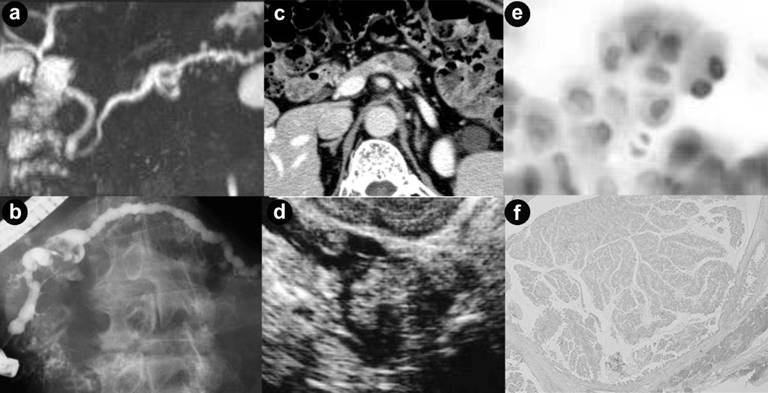

Morphological predictors of malignancy in BD-IPMNs were cyst size ≥30 mm [7, 9, 12], dilatation of MPD [10, 14], and presence of mural nodule [7, 9-13, 15]. Consistently, a very recent meta-analysis showed that these 3 factors were their indicators of malignancy (17). In the present study, analysis was performed using ROC curve in order to determine the cyst size, MPD diameter, and mural nodule size that could discriminate malignant from benign BD-IPMNs (Figure 2). Subsequent univariate and multivariate analysis by factors including these parameters showed that mural nodule size ≥10mm was the only predictor of malignancy except positive cytology of pancreatic juice. Presence of mural nodule was a strong indicator of malignancy in BD-IMMN [7, 9-13, 15], but their sizes have not been considered. In discrimination of malignant and benign BD-IPMNs, their sizes have to be taken into consideration, because IPMNs with larger nodules were shown likely to be malignant in a few studies that did not examine MD-IPMNs and BD-IPMNs separately [17-22]. Recently, by investigating BD-IPMNs exclusively, it was shown that the mural nodule sizes were significantly greater in malignant neoplasms than in benign ones (16.4 mm vs. 4.3 mm) [23]. In addition, it was reported that using cut off values of 5 mm and 7 mm, sensitivities and specificities for malignancy in BD-IPMN were 73% and 80%, 86% and 100%, respectively [24, 25]. A low sensitivity of 50% and a high specificity of 99% in the present study indicated that a substantial number of malignant BD-IPMNs had mural nodules <10 mm and few benign BD-IPMNs had mural nodules ≥10 mm. Moreover, because not a few malignant BD-IPMNs lacked mural nodule [22], discrimination of malignant from benign neoplasms by setting a cut off value is limited in accuracy. In order not to miss malignant BD-IPMNs in selecting candidate for surgery, another predictor of malignancy should be considered.

|

Figure 2. A representative case of malignant IPMN with nodule size of ≥10 mm in size and negative cytology. (a). Magnetic resonance pancreatography (MRP) showed a cyst of 15 mm in size at the pancreatic body and the diffuse dilated main pancreatic duct. (b). Endoscopic retrograde pancreatography (ERP) showed a filling defect in the cyst and peri-cystic area which indicated presence of mucus. Tip of the catheter used for aspiration of pancreatic juice was inserted into the cyst. (c, d). CT and endoscopic ultrasound showed a mural nodule of 15 mm in size inside the cyst. (e). Microscopic examination of pancreatic juice revealed hyperplastic cells which were classified into class II (Papanicolaou’s stain). Despite negative cytological result, the patient underwent surgery because of mural nodule of ≥10 mm in size. (f). Final diagnosis was determined as non-invasive intraductal papillary mucinous carcinoma by microscopic examination of the resected specimens. A mural nodule consisted of carcinomatous epithelia was observed inside the cyst at the pancreatic body. |